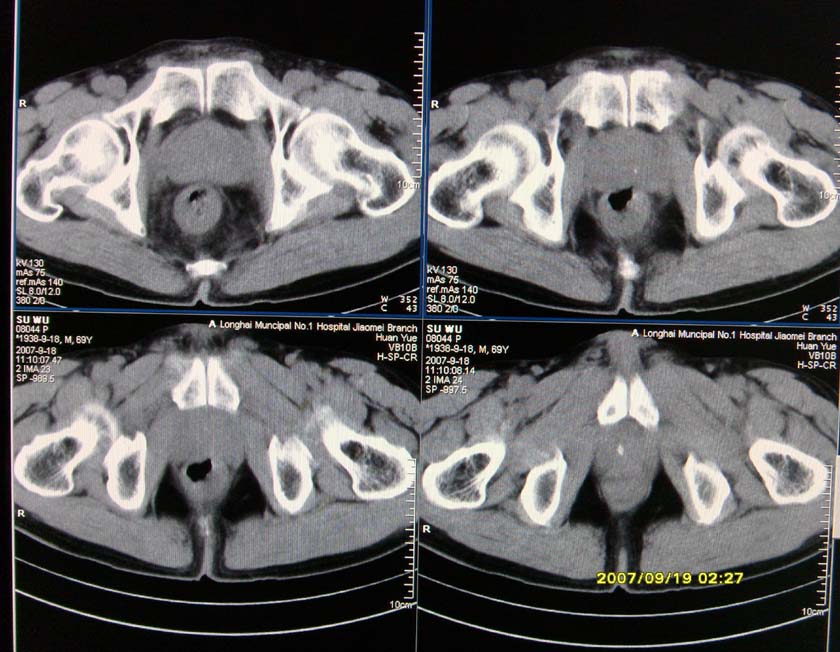

以下是引用xclzq_910在2007-9-19 16:58:00的发言:[br]直肠壁增厚,管腔偏移,直肠癌可能性大

以下是引用宝天曼在2007-9-19 21:11:00的发言:[br]根据直肠壁不规则增厚,考虑直肠肿瘤,不过最后的确诊还是需要肠镜.